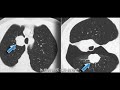

がん診療連携拠点病院院内がん登録 2008. 年度第1 回都道府県がん診療連携拠点病院連絡協議会がん登録部会での検討に基づき、施 設別の生存率について集計を. 肺癌 wikipedia. 肺癌(はいがん、英Lung cancer)は、肺に発生する上皮細胞由来の悪性腫瘍。90%以上が気管支原性癌 (bronchogenic carcinoma. 肺癌に対する“切らない”で治す低侵襲治療『局所麻酔下の凍結治療』. 肺癌に対する“切らずに治す低侵襲治療”『局所麻酔下の凍結治療』について説明しています。. 胃がんステージthreeの症状とは?3a、3b、3cの生存率や余命. 今回は、胃がんのステージ3についてご紹介します。胃がんステージ3ではどのような症状が表れるのか、その生存率や余命. 肺癌 chijimatsu. 今年の1月肺の小細胞ガンと診断され、2月から11月までに6回の抗がん剤の 点滴をしました10月まで大変元気にして. 膀胱癌の再発と予後(生存率)~検診は必要・有用か?予防策は?. 癌の治療後の再発と予後は、患者本人もしくは患者家族が最も心配する部分ではないでしょうか?ここでは、臨床医学的に.

肺癌に対する“切らない”で治す低侵襲治療『局所麻酔下. 肺癌に対する“切らずに治す低侵襲治療”『局所麻酔下の凍結治療』について説明しています。. Ebmの手法による肺癌診療ガイドライン2014年版. A. 副腎転移に対する外科的切除の検討として,非小細胞肺癌を含む固形癌の30症例を対象とした報告があり,副腎単発症例. 肺がんステージ4から完治する方法【私が1年持ったコ. 肺がんステージfourから完治することはできるのか?手術できない癌に対してできる治療方法と、私が告知から1年余命を保ち. 切除後の肺機能と生存率 医療ポータルサイト. 切除後の肺機能と生存率について解説しています。. 各期肺癌的五年生存率,就是大家说的还能活多久 好大夫在线. 在2015年的数据统计中,我国肺癌的发病率为733/10万,死亡率为610/10万,均位列世界第一。到2025年,我国每年仅死于肺癌的. 肺癌 chijimatsu. 今年の1月肺の小細胞ガンと診断され、2月から11月までに6回の抗がん剤の 点滴をしました10月まで大変元気にして. 癌と共に生きる 手術→放射線治療→化学治療. 肺がんと闘病した1年間、順調に見えて壮絶だった母が永眠。残された半身麻痺で要介護の父・・・毎日思いのままに語って. 漢方生薬治療による脳転移の肺癌の長期生存例 てつろぐ. 大学病院で診療していた頃、脳など全身に転移した末期の原発性肺癌患者の治療を行った。抗がん剤、免疫療法を行った後.